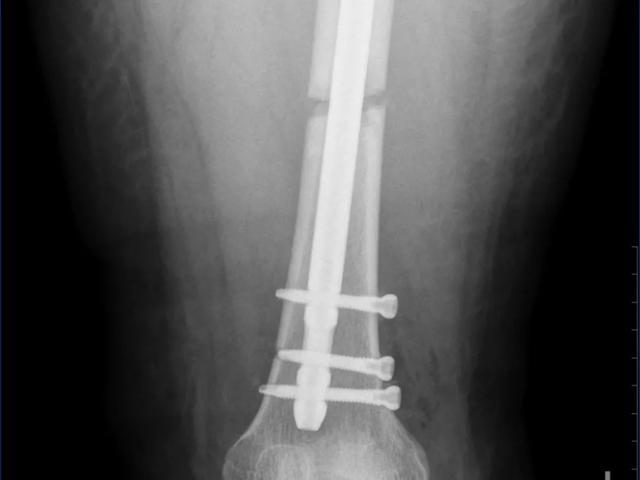

经过深思熟虑和反复推演,与王女士及其家属充分沟通后,骨二科团队决定采用微创手术方案,为王女士行闭合复位髓内钉内固定手术治疗,稳定骨折端,重塑下肢力线。

(术后)

手术室内,C型臂X光机如同医生的“第三只眼”,实时捕捉着导针在骨髓腔内的行进轨迹。主刀医生凭借着丰富的经验和精湛的技术,通过股骨近端6厘米的单一切口,利用弹性导针完成了双骨折段的“串珠式”精准复位,全程未损伤任何肌肉组织。术后王女士安返病房,目前恢复良好。